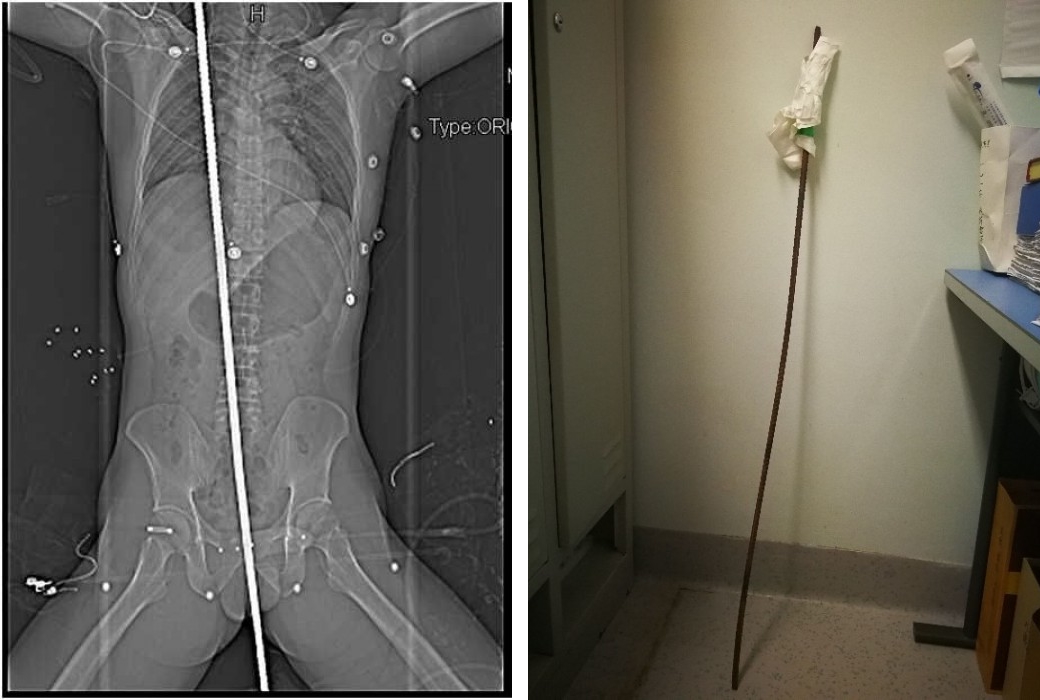

그 아래에는 지름 1cm 정도 되는 철근이 수직 방향으로 설치되어 있었는데 그곳으로 떨어지면서 철근이 항문 부근을 찌르고 몸통을 관통하여 오른쪽 어깨 부근까지 이르렀습니다.

남성은 곧장 성도시내에 있는 사천대학 화서병원으로 긴급 이송되었고 누가 봐도 지극히 심각한 사태의 이 환자에 대하여 의사들은 즉시 엑스레이 촬영 등을 실시했는데 다행히 체내에서 대출혈이 발생한 징후는 보이지 않았습니다.

먼저 남성의 흉강과 복강을 열어보니 항문 부근에서 남성 몸에 들어간 철근은 방광과 직장 사이를 통과했는데 통상 방광과 직장은 서로 붙어 있는 것 같이 좁은 상태인데 철근이 그 빈틈을 통과하고 있다는, 거의 상상할 수 없는 기적이 처음부터 시작되고 있었습니다.

이후 철근은 복강 내에서도 큰 혈관에는 부딪치지 않았고, 소장의 일부를 상처 입히면서 췌장에 거의 붙다시피 통과가 되어 지나갔습니다.

췌장, 십이지장, 담낭 등 복잡한 장기 중 어느 하나라도 손상이 되었으면 수술은 극히 어려워지는데 철근은 간 뒷부분을 지나 왼쪽 폐에 꽂혀 있었다고 합니다.

의사는 혈관이 많은 오른쪽 폐에 들어가면 남성은 참을 수 없었을 것이라고 말했는데 이도 천운이네요.

철근은 심장을 빗질하듯이 지나고 오른쪽 상단으로 향한 후 남성의 맨 위 오른쪽 갈비뼈 아래에서 멈춰 있습니다.

의사들에 따르면, 철근이 더 위의 쇄골 부분에 도달했다면 중요한 동맥이나 정맥을 찔러서 아주 위험했을 것이라 하네요.

의사들은 손상된 폐와 간의 일부를 절제하고 손상된 소장을 꿰맨 후 두께 1cm, 길이 1.2m의 철근을 뽑아냈다고 합니다.

의사의 말로는 이 남성이 살아난 가장 큰 이유는 철근이 중요한 혈관을 하나도 해치지 않았기 때문이라고 하는데 철근이 어느 부위의 혈관에 꽂혀 있어도 생존은 어려웠을 것이라고 합니다.

좌측 엑스레이 사진이 철근이 항문에서 어깨까지 관통하여 박혀진 사진이고 우측은 몸에서 빼낸 철근.